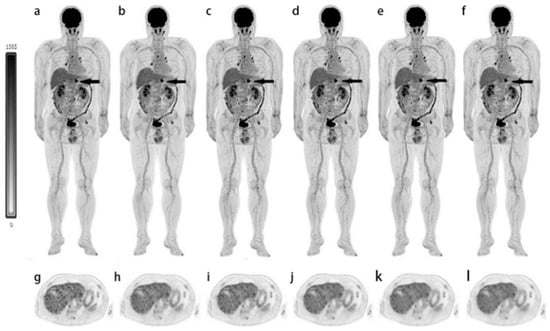

- Wang, G.; Nardo, L.; Parikh, M.; Abdelhafez, Y.G.; Li, E.; Spencer, B.A.; Qi, J.; Jones, T.; Cherry, S.R.; Badawi, R.D. Total-Body PET Multiparametric Imaging of Cancer Using a Voxelwise Strategy of Compartmental Modeling. J. Nucl. Med. 2022, 63, 1274–1281. [Google Scholar] [CrossRef]